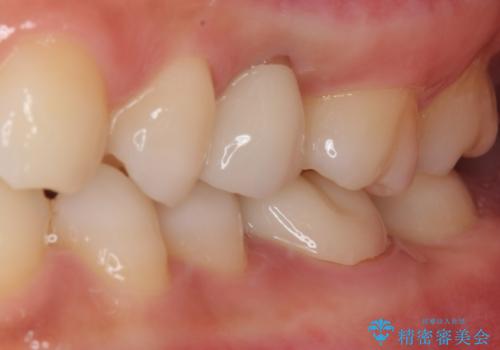

- 左上が虫歯になった気がするとのことで来院された患者様です。

左上の七番目と六番目の歯と歯が接するところに虫歯をレントゲン上で確認できました。

噛み合わせが強く、以前にも当院で右上でゴールドインレーにより治療をされていたのでゴールドインレーにて治療しました。

拡大鏡視野下で、虫歯の除去を行い、ゴールドインレーに適した形に整えました。